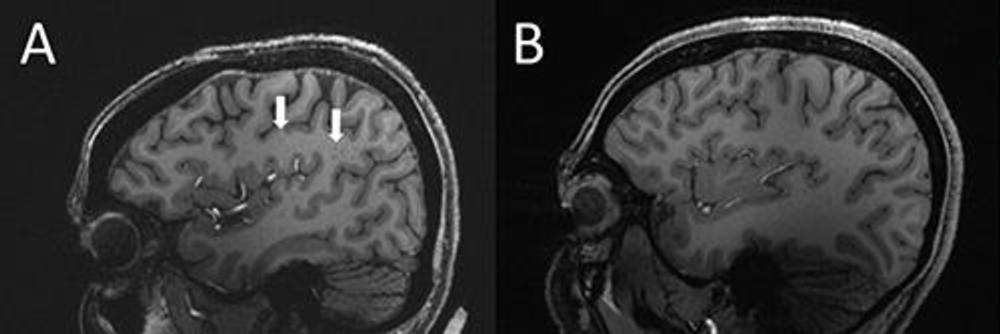

Figure 4. (A) Enlarged centrum semiovale (CSO) perivascular spaces (PVS) (arrows) on sagittal T1-weighted MRI in a case with chronic migraine. (B) Migraine-free control without enlarged CSO PVS.